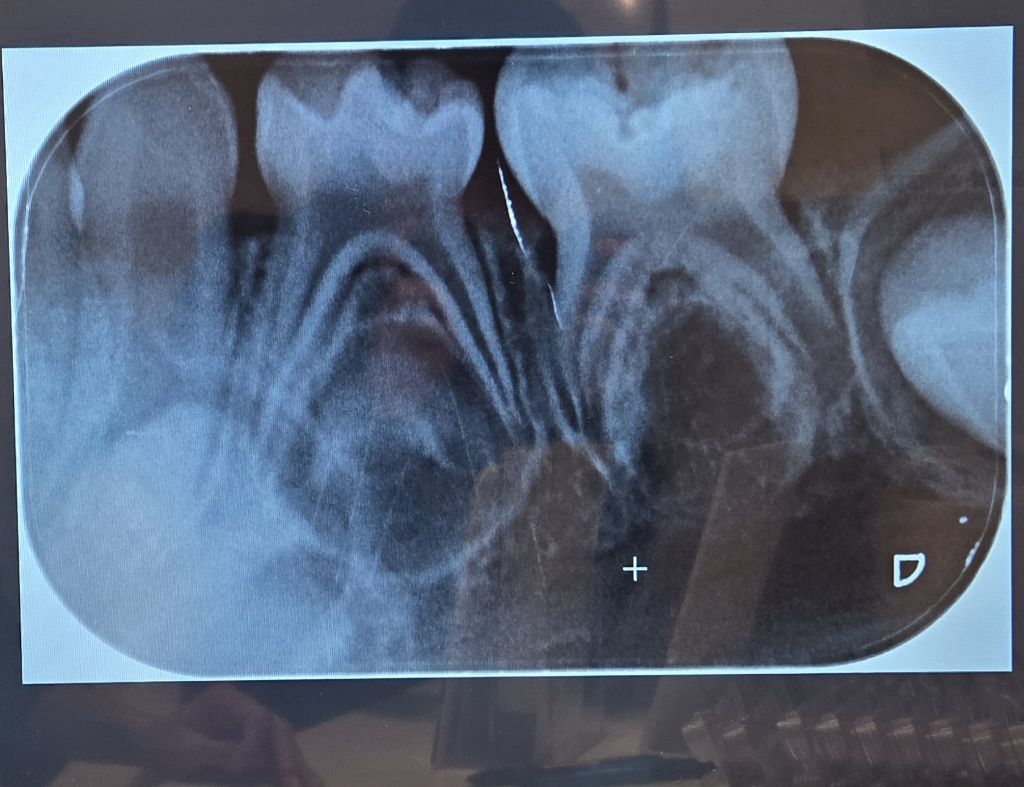

선생님 치과 방문도 계획했으나 전화문의 결과 너무 어려서 엑스레이 찍을 도구도 마땅치 않다는 안내에

일단 동네 어린이치과에서 엑스레이를 찍은 후 부탁해 사진을 받아 왔습니다.

이 치과에서는 모든 어금니에 충치가 다 있으나 (보는 사람 기준) 왼쪽 위에는 매우 약해서 치료를 안 해도 될 수는 있다고 했습니다만 나머지 6개는 모두 치료가 필요하다고 했습니다.

씹는면 충치만 있을 뿐 사이 충치가 없어서

버티는 방법을 실행해 볼 수도 있습니다.

물론 아이들의 씹는면 충치는 빠르게 진행되는 경우가 많습니다.

집에서 식생활, 양치질 관리하면서 버티다가

구멍이 커지면

1개씩 레진/ GI 또는

아프면 신경치료 +크라운

이런 방식을 권하고 싶습니다만